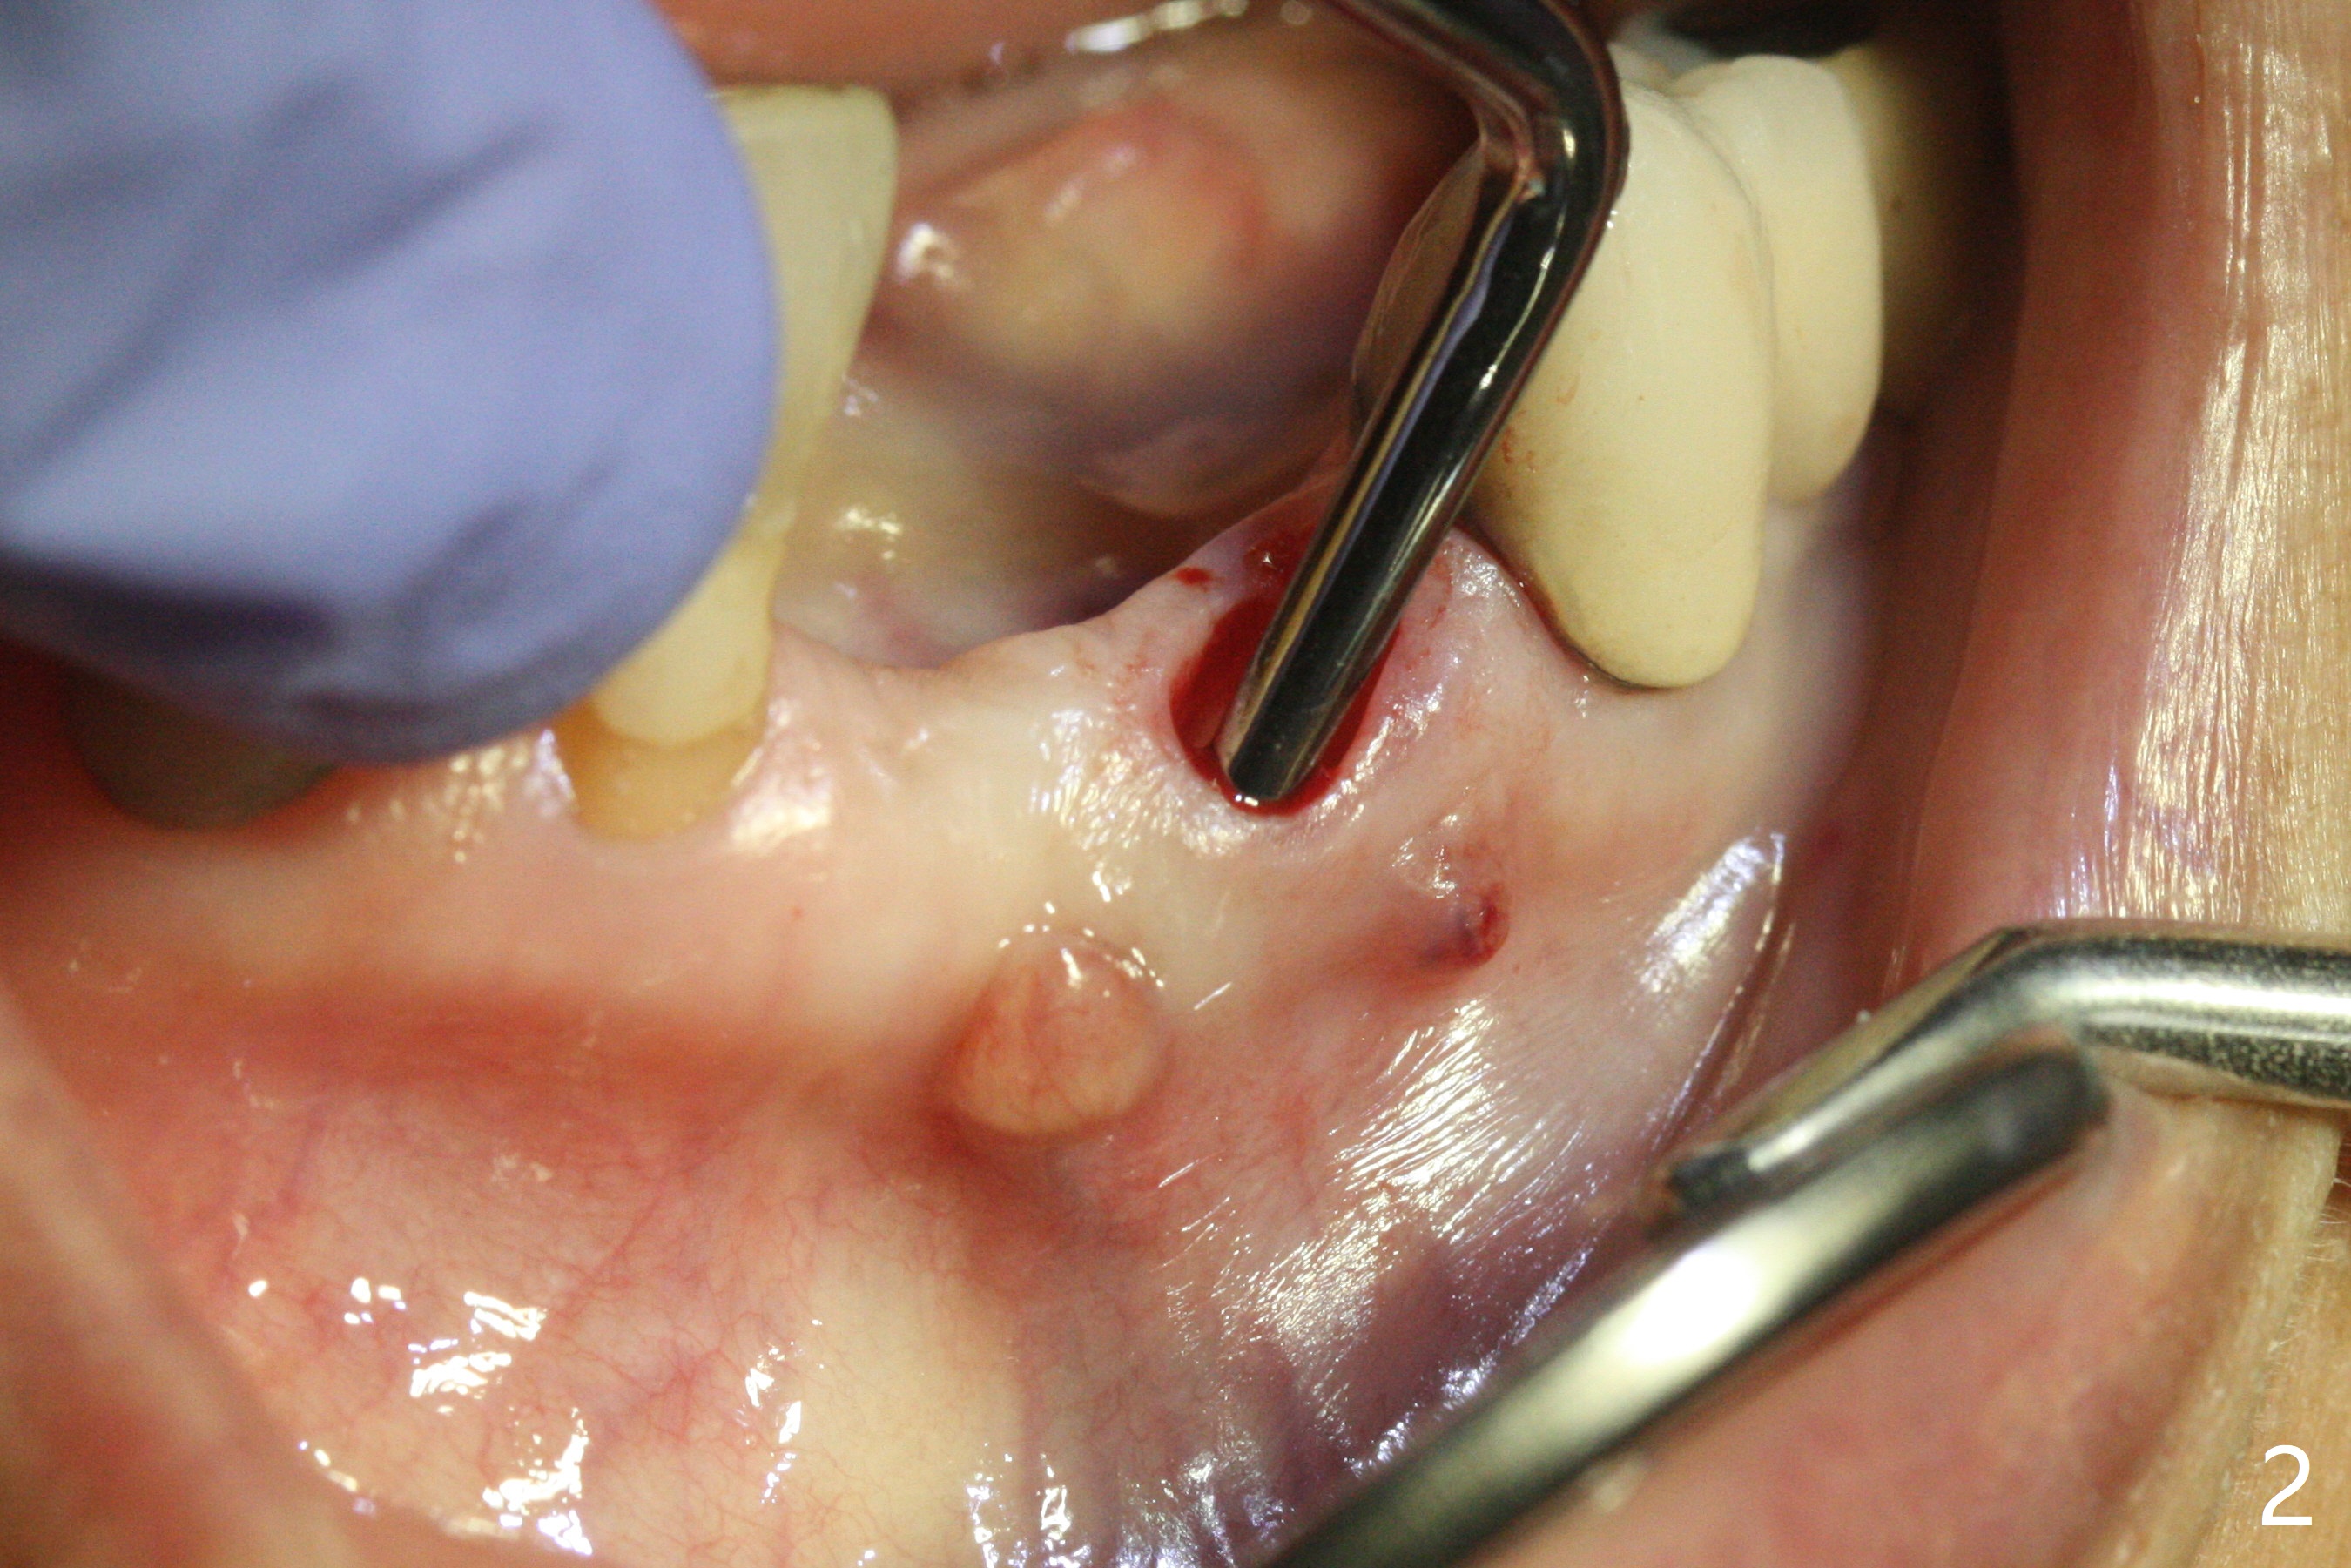

A 64-year-old woman requests extraction of the tooth #23 for lower partial (Fig.1). Since there are 2 buccal sinus tracks, another residual root is suspected (?). After shown loss of the buccal plate (Fig.2,3), the patient agrees to have socket preservation with allograft (Fig.5,6 *) and BioXclude (Fig.4 >). The suspected residual root is not explored considering the 2 sinus tracks being associated with the lesion of #23 (Fig.2,3). Cytoplast is not used because of time constraint and fear of gingival dehiscence associated with extensive dissection. In fact the sinus tracks shrink in a week, while the buccal plate remains bulging (Fig.7 *) and the socket heals (Fig.8 >). The buccal plate is flat (no swelling) 1 month postop (Fig.9).